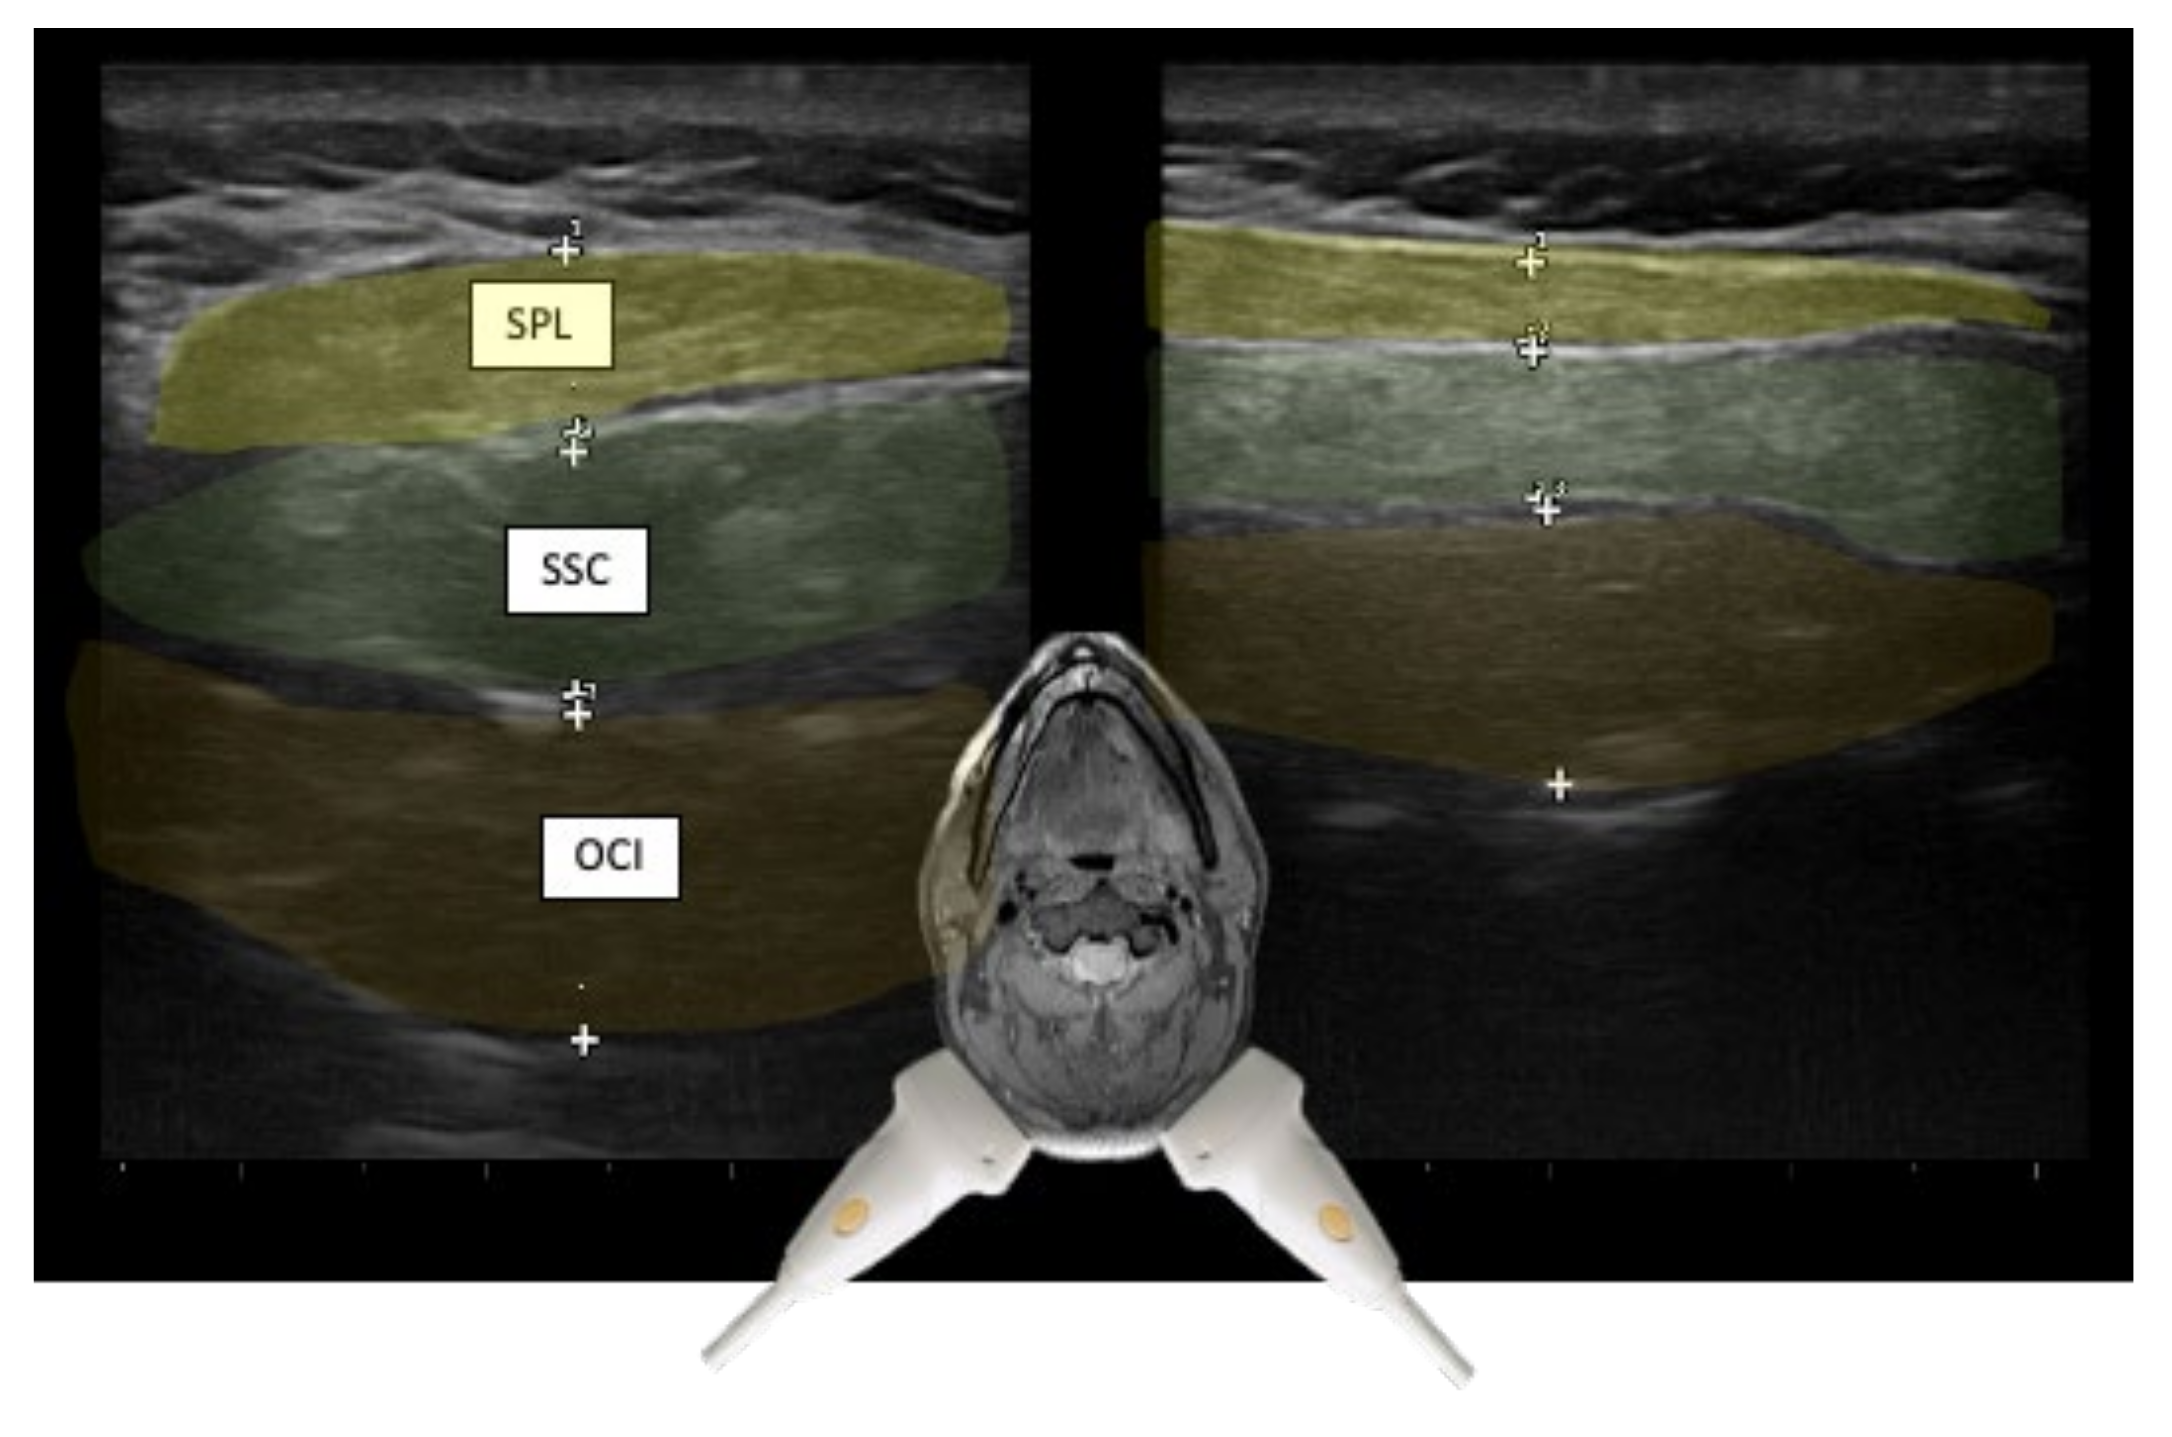

| Semispinalis capitis (SSPcap) | Extension of head | + | + | SPLcap, OCI | Strongest extensor muscle of head and neck |

| Semispinalis cervicis (SSPcer) | Extension of neck | + | + | SPLcer, TRA | |

| Splenius capitis (SPLcap) | Ipsiversion of head | ++ | ++ | major occipital nerve, SPLcap/cer, LSMcap, OCI | Prominent reduction in bulk from repeated injections possible |

| Splenius cervicis (SPLcer) | Ipsiversion of neck | +++ | ++ | LEV, TRA, Longissimus cervicis | Relevant for full turn of the neck |

| Obliquus capitis inferior (OCI) | Ipsiversion of head | +++ | +++ | SSPcap, RCM, vertebral artery, greater occipital nerve | Adjacent muscles are all extensors of the head |